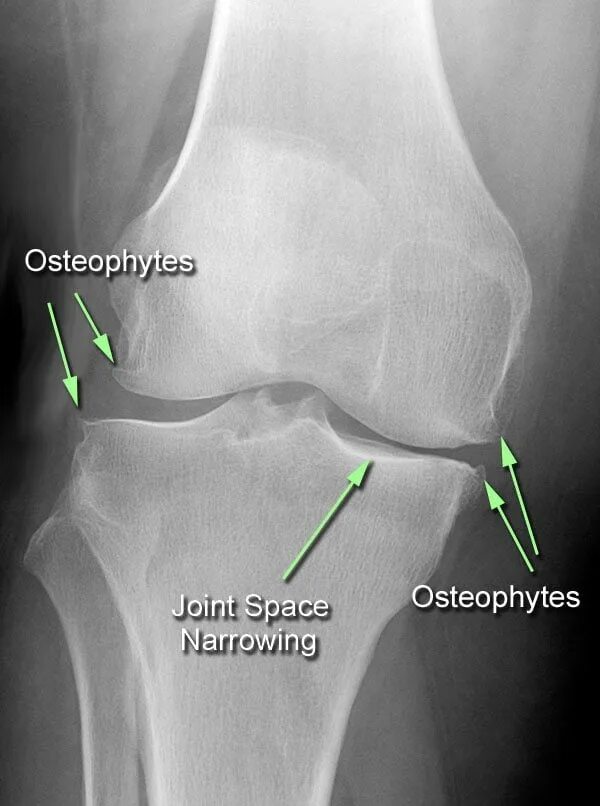

Лечение остеофитов сустав